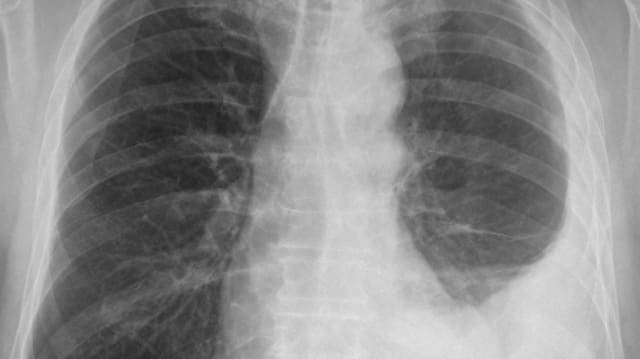

Ständerat Damian Müller will bessere Qualitätskontrollen bei Röntgenuntersuchungen in Schweizer Arztpraxen. Der Luzerner FDP-Politiker, Berater bei der Ärzteverbindung FMH und Präsident des Forums Gesundheit Schweiz, sieht Qualitätsmängel. Er verweist in einem Postulat auf eine Untersuchung vor fünf Jahren, die in Bezug auf die Bildqualität ein nennenswertes Verbesserungspotenzial zeigte. In der Schweiz werden jährlich insgesamt rund sechs Millionen Röntgenaufnahmen gemacht.

Heute erfolgen die Einhaltung der Vorschriften durch eine jährliche Eigenevaluation durch den Bewilligungsinhaber. Ihm schwebt aber das Modell externer Qualitätskontrollen vor, wie etwa in Deutschland. Dort kümmert sich eine ärztliche Stelle um die Verbesserung des Qualitätsniveaus radiologischer Untersuchungen und um den bestmöglichen Strahlenschutz. Müller erhofft sich tiefere Gesundheitskosten durch Vermeidung von doppelten und mehrfachen Röntgenbildern und weniger Strahlenbelastung. Der Politiker schätzt das Sparpotenzial vorsichtig gerechnet auf jährlich 30 Millionen Franken.